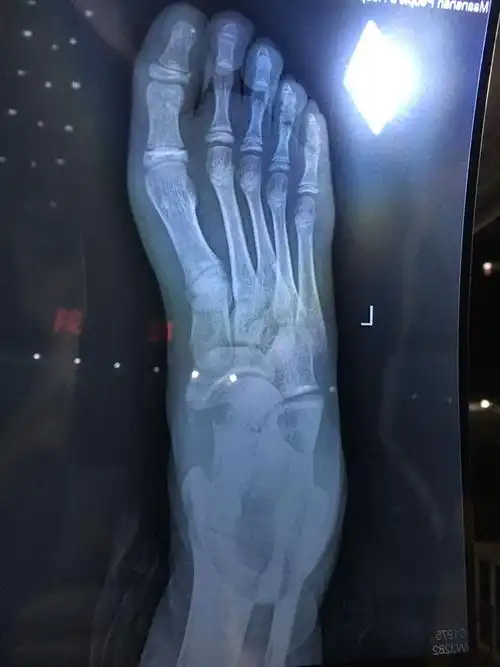

"香港新一代玉女"卫诗雅滑雪时发生意外:脚骨裂了五分之四!